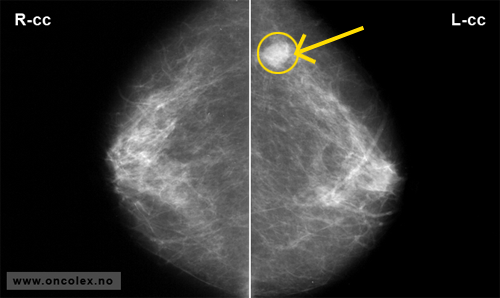

Eksempler på mammografibilder

Mammografi horisontalt plan (frontprojeksjon) av begge bryst. Ingen sykelige funn.

Mammografi horisontalt plan (frontprojeksjon) av begge bryst. Suspekt fortetning i venstre bryst.